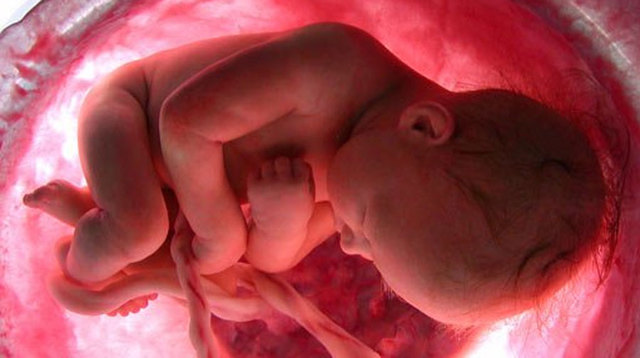

• 4 meses. Características externas

4 meses. Características externas

-La piel es delgada, traslúcida, es fácil ver los vasos sanguíneos debajo de ella

-Las narinas están casi formadas

-El feto puede comenzar a chuparse el pulgar

-Los ojos se han despalzado hacia la parte frontal de la cara

-Las piernas son más largas que los brazos

-Aparece un lanugo fino en el cuero cabelludo

-Las uñas de la mano están bien formadas; se están formando

las de los pies

-Aparecen los pliegues epidérmicos en los dedos

-La madre puede sentir los movimientos fetales